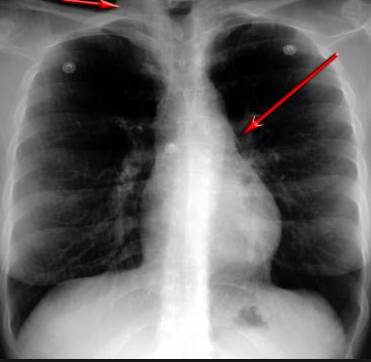

這臺4D掃描儀

能讓醫生有一雙可以透視的眼睛

整個肺部看得清清楚楚!

4D高清透視!

使用這臺掃描儀,將直接把器官變成3D圖形!細微的毛細血管,幾毫米大的肺泡和支氣管,都將能看的一清二楚!

你的每一個氣泡,每一段支氣管,哪兒有病變都清清楚楚的將展示在醫生面前!

也就是說在一切都還沒開始惡化前,把這些有問題的器官組織都暴露的一清二楚:

不只是圖形,還是動態的!

這臺儀器不僅僅是一臺能拯救幾百萬條生命的高清掃描儀,它更是一場開天辟地的技術革新!因為它不僅能幫醫生看到肺病的結構圖,

還能看到器官是如何運動的!

空氣是如何進入到肺部,氧氣是如何到血液,任何微小的變化都將曝露在醫生面前!更清晰的圖像,更細節的變化!